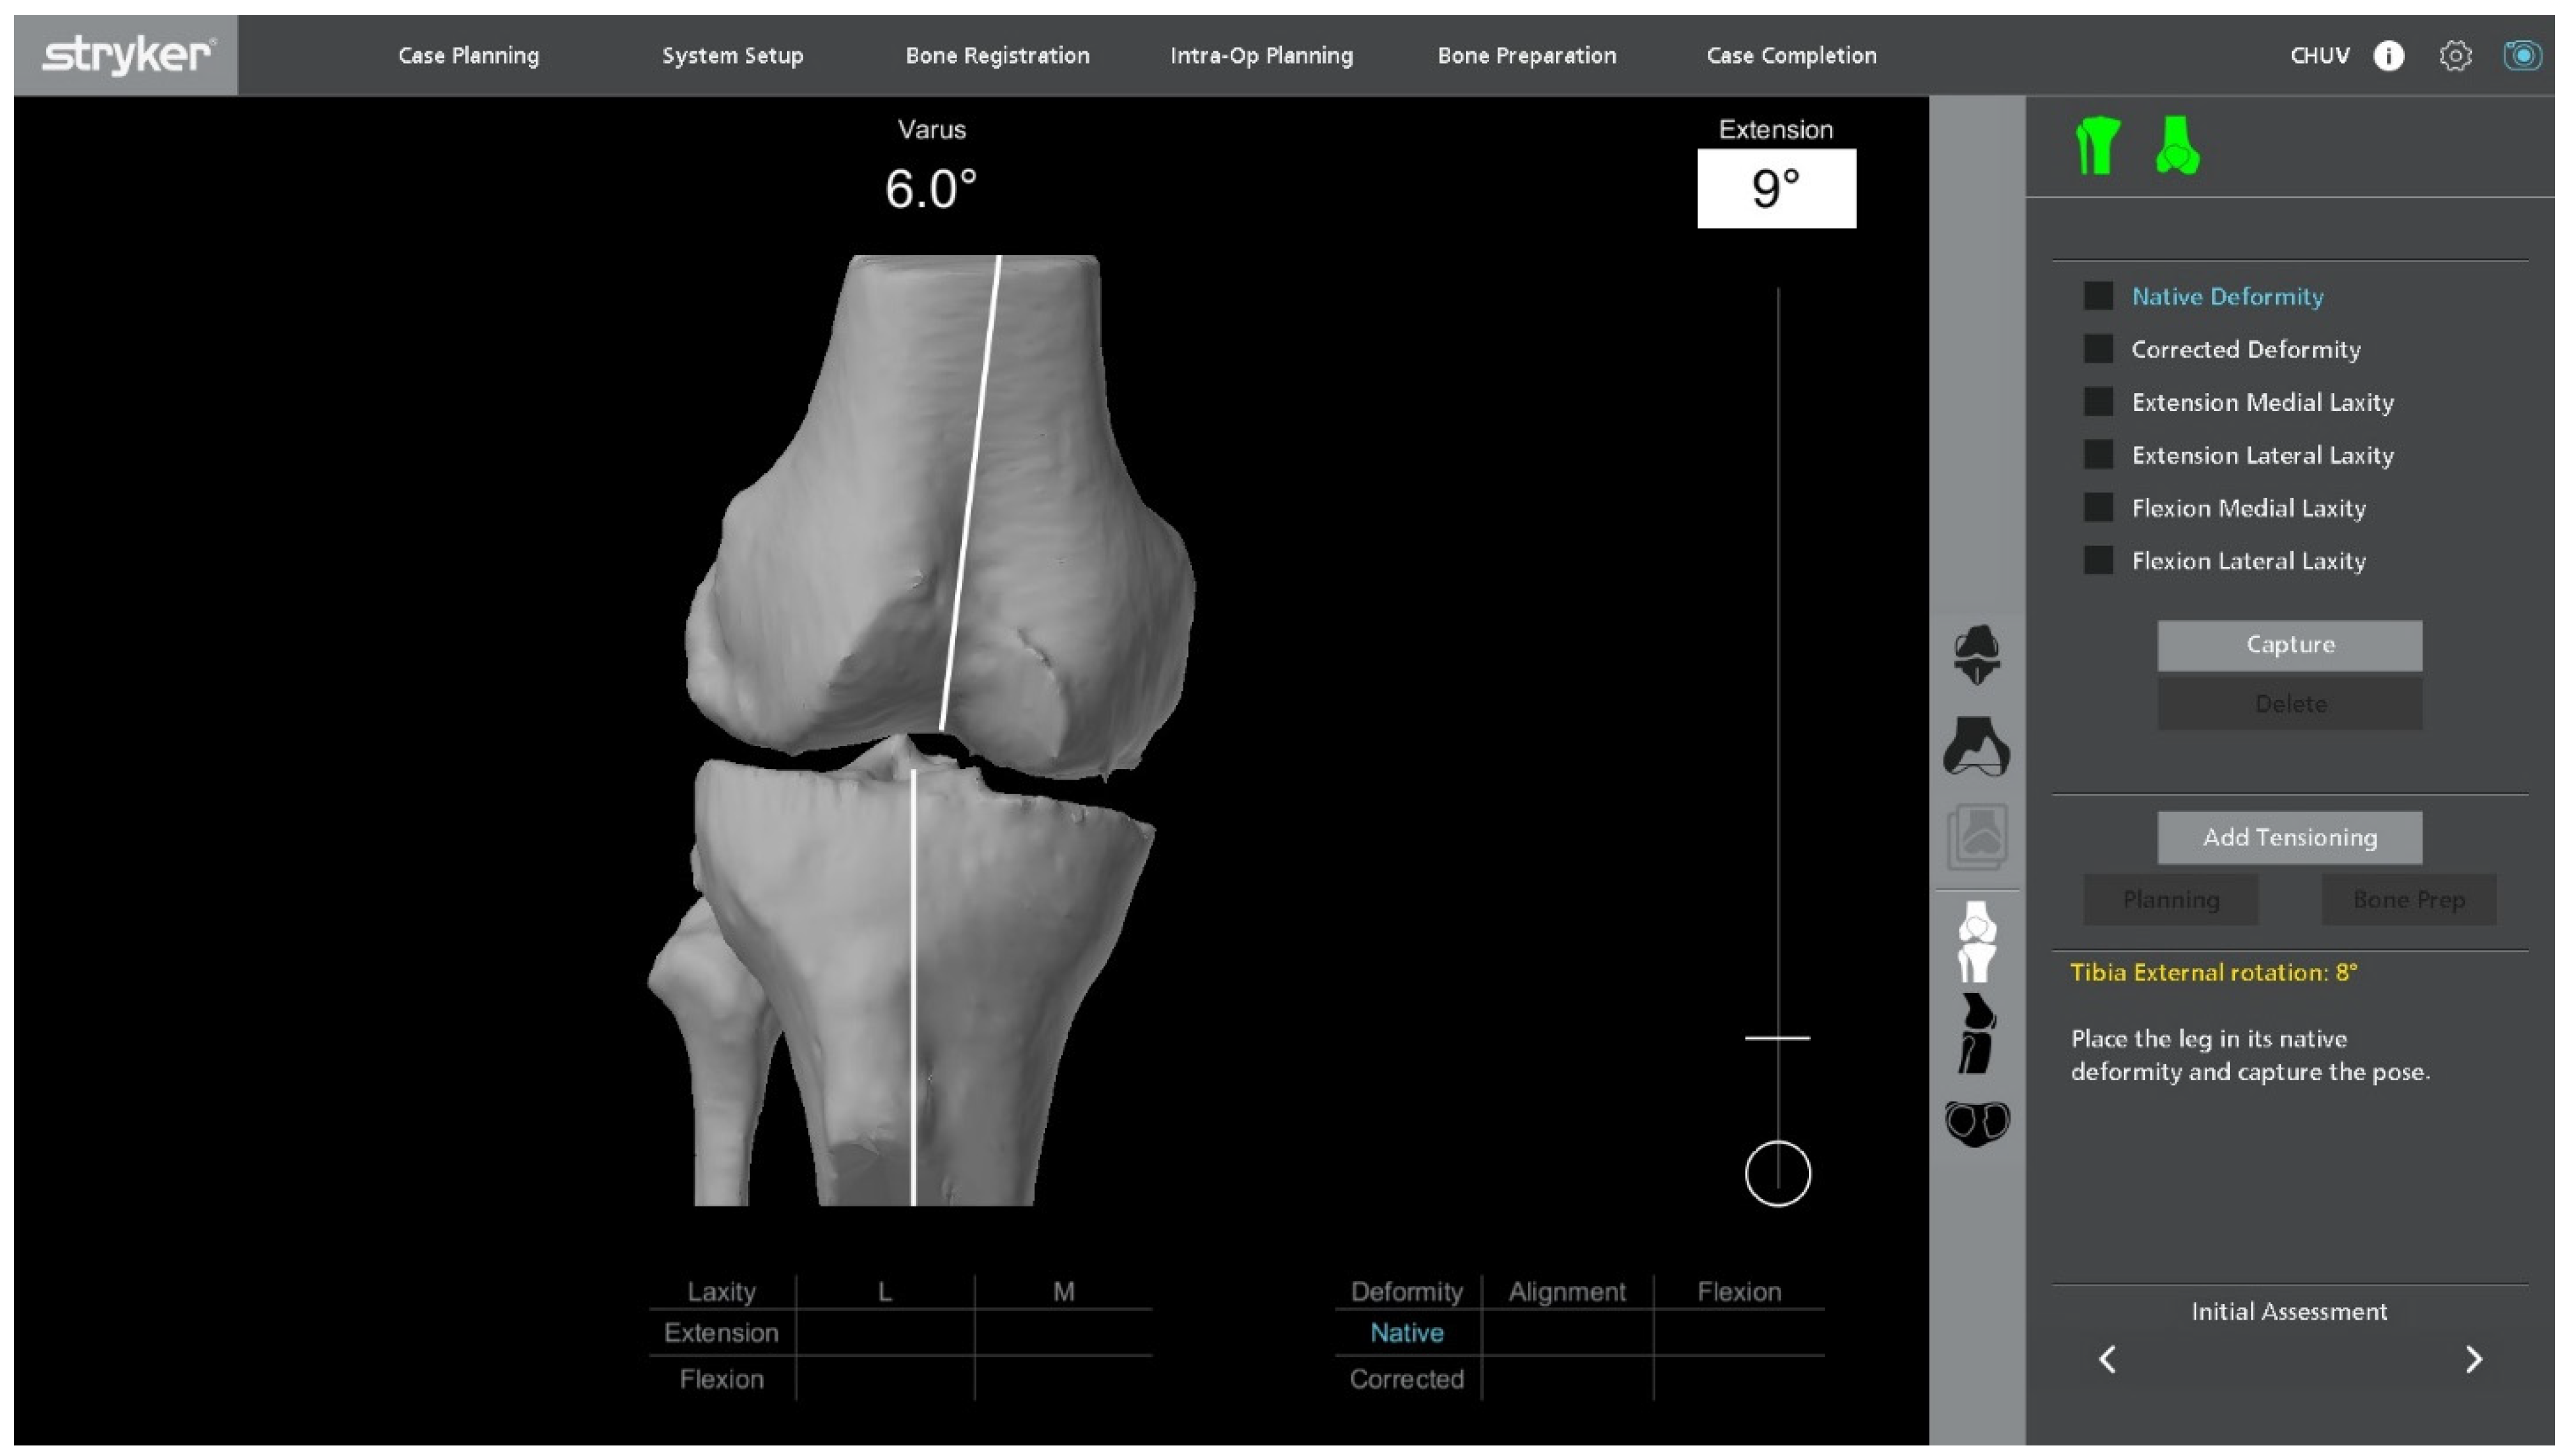

2.8. Final Implantation

Trial components are inserted to confirm flexion–extension gap balance and overall stability (Figure 7). At this stage, balance is assessed both without stress and under standardized varus-valgus stress in terminal extension and at 90° of flexion. Once satisfactory alignment and soft-tissue tension are achieved, definitive cementless condylar-stabilizing components are implanted (Figure 8). We favor CS inserts to obtain coronal stability without ligament releases and without a cam-post mechanism, consistent with bone preservation. Cruciate-retaining implants are used only when the posterior cruciate ligament is clearly competent, and posterior-stabilized (or revision) constructs are selected when anteroposterior stability cannot be ensured with CS inserts or when ligament competence or bone stock are insufficient. Stems, augments, or ligament releases are typically not required. The patella is systematically resurfaced to decrease the risk of future anterior knee pain and revision surgery. Ensure that the final implant position matches the 3D planning and that all the implant press-fit interfaces are fully seated before closure.

Figure 7.

Ligament balancing testing with trial components in place, confirming stable flexion–extension gaps prior to final implantation.

Figure 8.

Final implantation of CS TKA with patellar resurfacing.